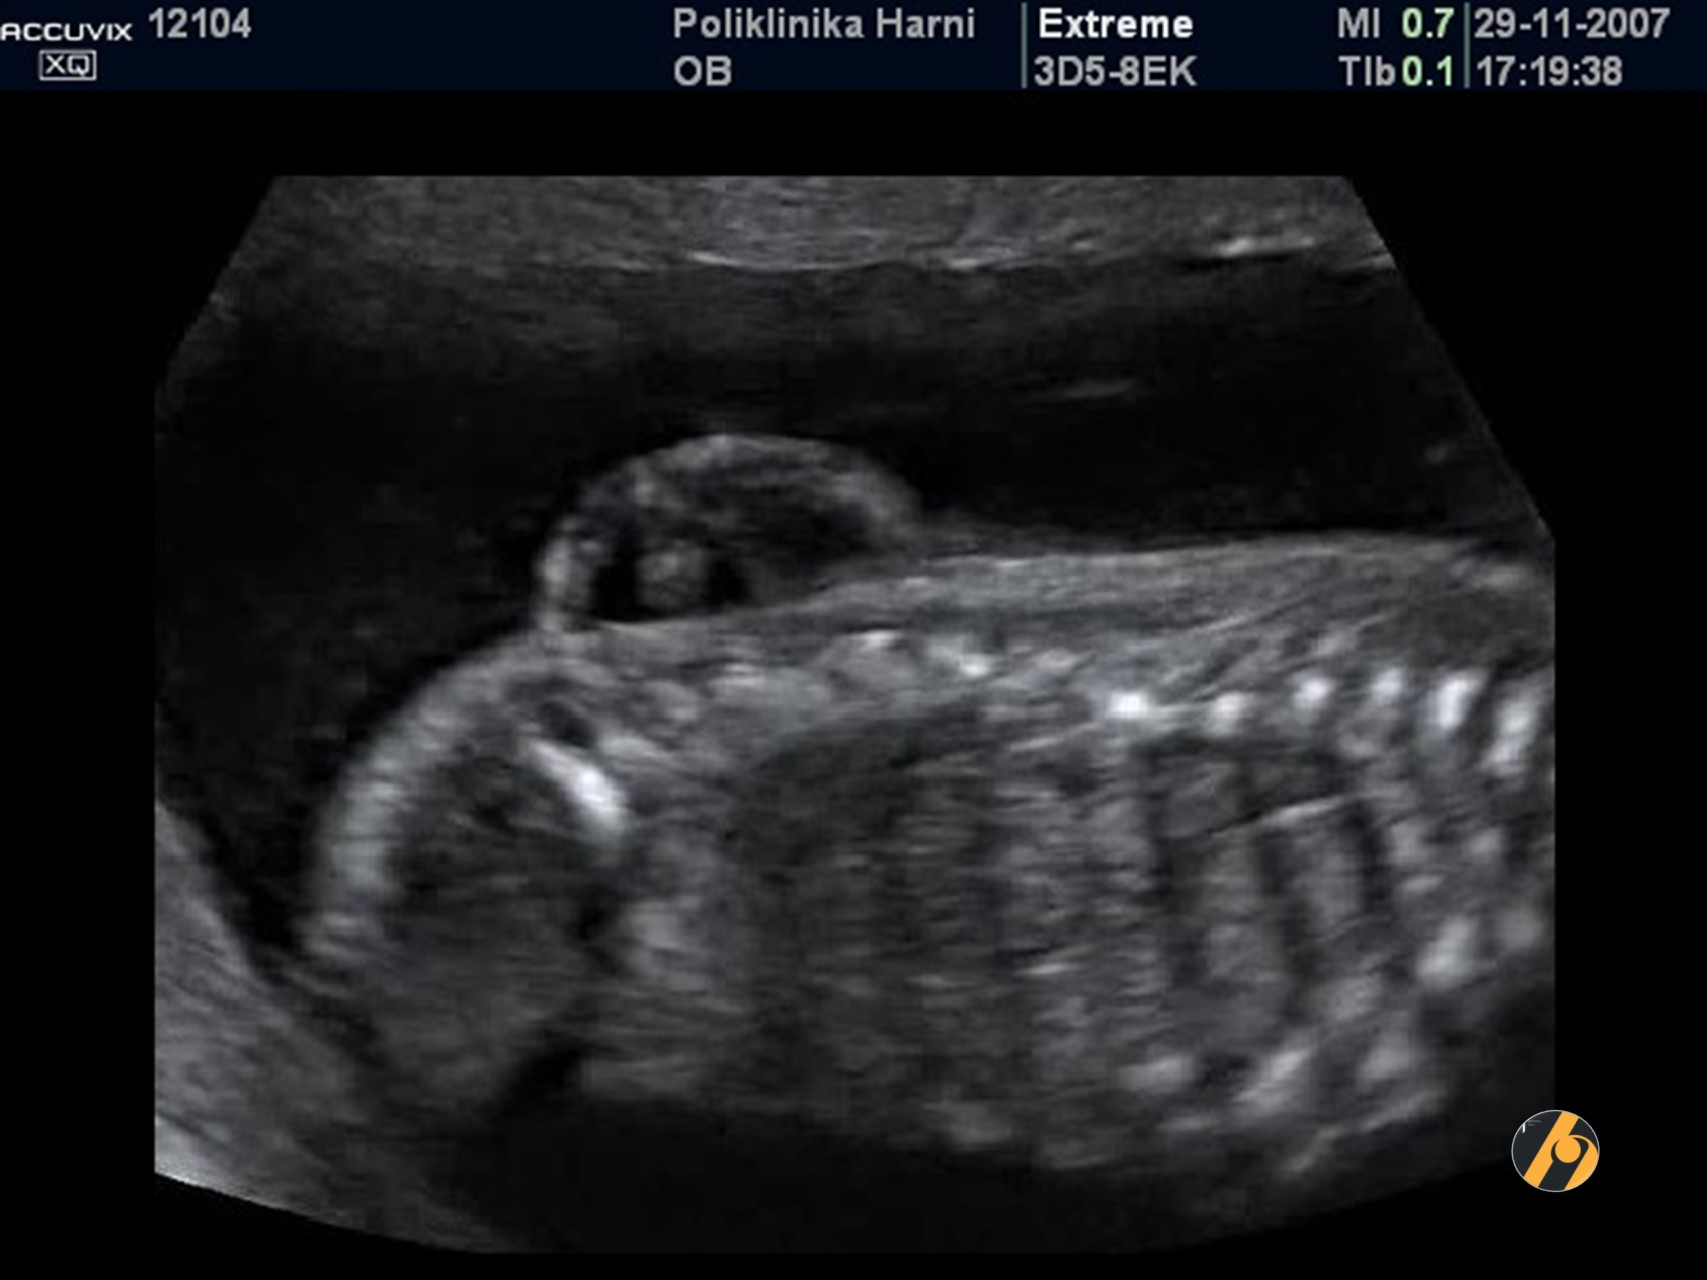

Slika prikazuje aplaziju radijusa s tipično medijalno postavljenom šakicom pod kutom od 90°.